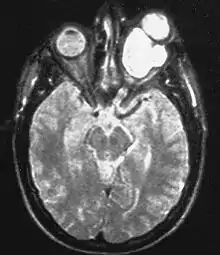

Magnetic resonance image of a large retrobulbar optic nerve tumor causing massive proptosis

Optic nerve gliomas are diagnosed using magnetic resonance imaging (MRI) and CT scans.[5] The tumor adopts a fusiform appearance, appearing wider in the middle and tapered at the ends.[5] Enlargement of the optic nerve along with a downward kink in the mid-orbit is usually observed.[5] While CT scans allow for optic nerve evaluation, MRI allows for intracranial evaluation to observe if the tumor has extended to other regions such as the optic chiasm & hypothalamus.[6]